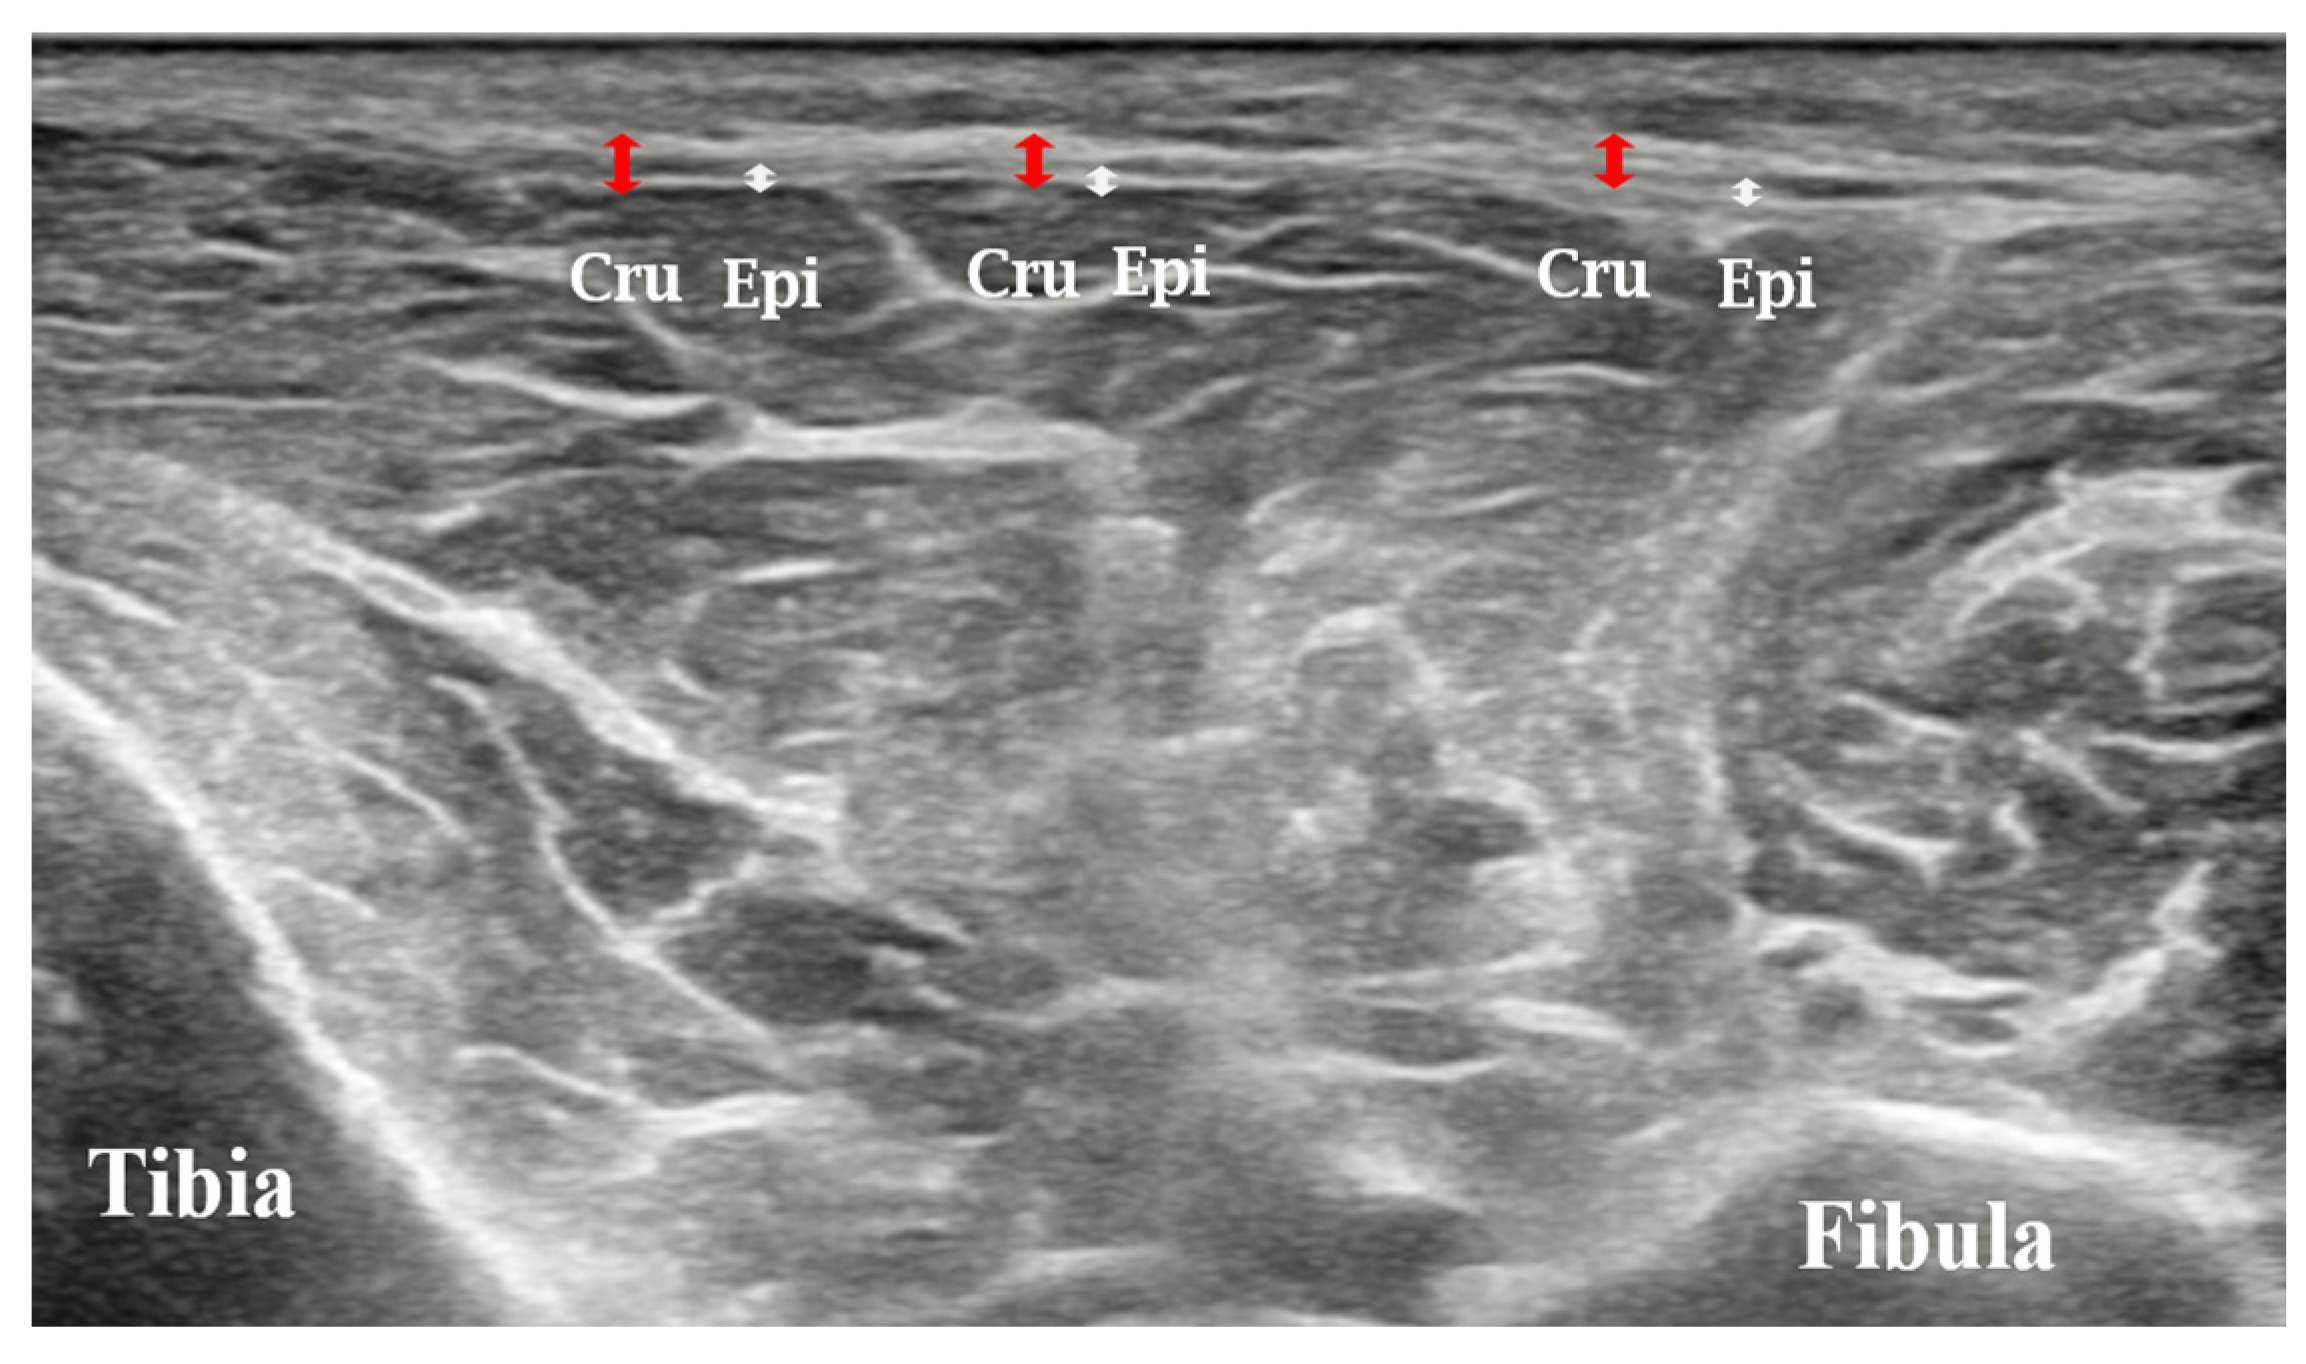

2.3.2. Fascia Thickness

| Anterior compartment of crural fascia | 0.96 ± 0.14 | 0.72 ± 0.08 | <0.001 |

| Lateral compartment of crural fascia | 1.01 ± 0.14 | 0.75 ± 0.14 | <0.001 |

| Posterior compartment of crural fascia 1 | 0.92 ± 0.22 | 0.68 ± 0.11 | <0.001 |

| Posterior compartment of crural fascia 2 | 0.96 ± 0.21 | 0.72 ± 0.16 | <0.001 |

| Posterior compartment of crural fascia 3 | 1.02 ± 0.30 | 0.77 ± 0.16 | <0.001 |

| Tibialis anterior epimysial fascia | 0.46 ± 0.07 | 0.34 ± 0.03 | <0.001 |